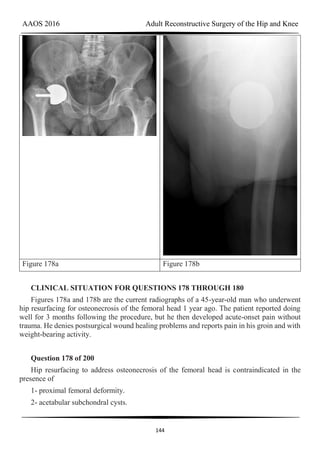

7- Cementless acetabular revision

8- Isolated liner/head exchange

9- Isolated liner/head exchange with cementing of the liner

Select the most appropriate treatment for each clinical scenario.

Question 76 of 200

A 72-year-old man with a history of prior revision for a loose femoral component (Figures

76a and 76b)

1- Cemented full revision

2- Cemented femoral revision

AAOS 2016 Adult Reconstructive Surgery of the Hip and Knee

65

3- Cemented acetabular revision

4- Cementless full revision

5- Cementless femoral revision without an extended trochanteric osteotomy

6- Cementless femoral revision with an extended trochanteric osteotomy

PREFERRED RESPONSE: 6- Cementless femoral revision with an extended trochanteric

osteotomy

Question 77 of 200

A 65-year-old woman with intraoperative findings of well-fixed components and a

deficient liner locking mechanism (Figures 77a and 77b)

PREFERRED RESPONSE: 7- Cementless acetabular revision

Question 78 of 200

A 68-year-old woman with a history of thigh pain on startup since her primary total hip

arthroplasty (THA) 1 year ago (Figures 78a and 78b)

66

PREFERRED RESPONSE: 5- Cementless femoral revision without an extended

trochanteric osteotomy

Question 79 of 200